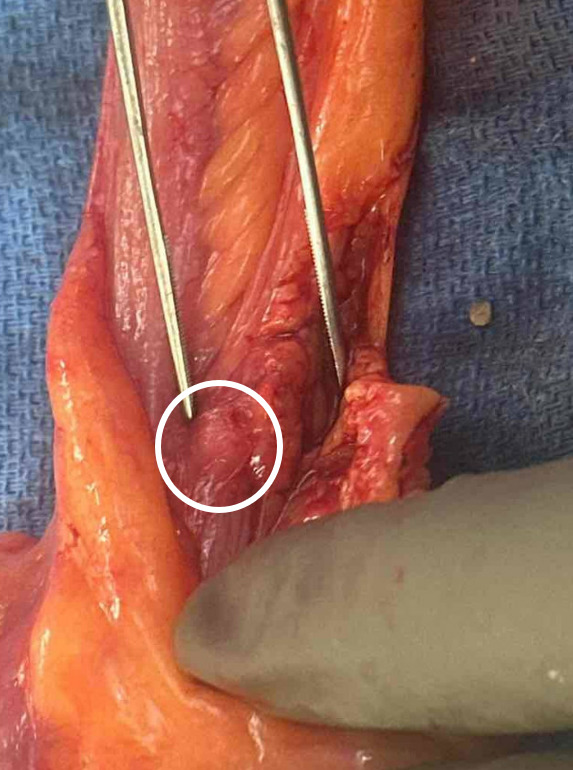

由于梅克尔憩室位置不典型导致大量下消化道出血。

Massive lower gastrointestinal bleeding due to Meckel's diverticulum in an atypical position.